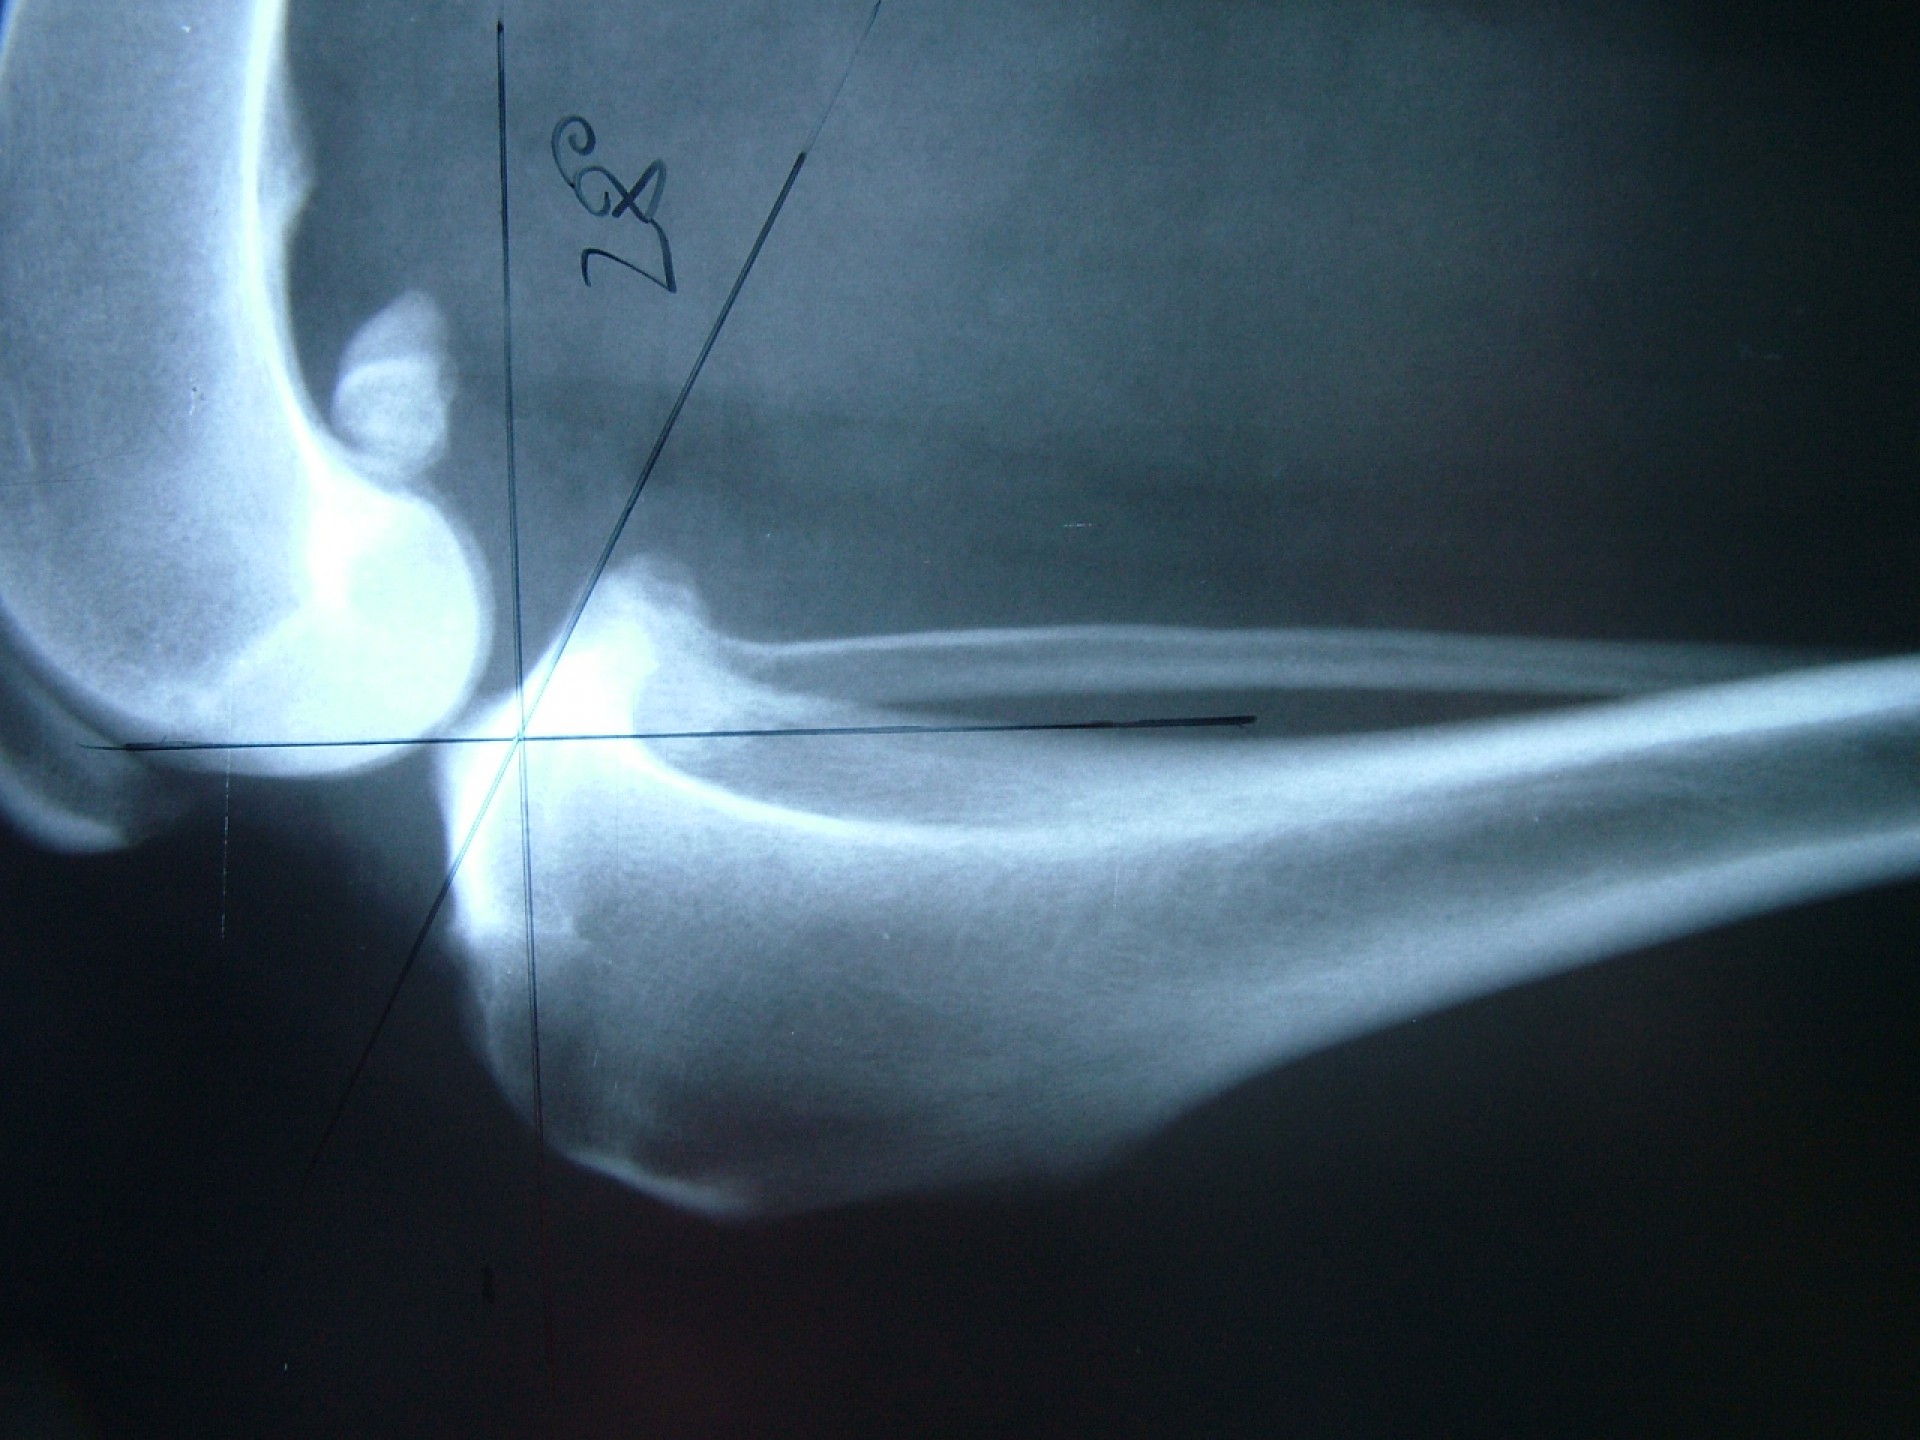

Az utóbbi 25 év egyik legnagyobb előrelépését jelentette a kereszteződőszalag szakadás műtéti megoldásában az amerikai származású Barclay Slocum által kifejlesztett műtéttechnika, mely alapja a szakadásra hajlamosító tényezők és a szalagra ható fizikai erők vizsgálata. Barclay Slocum olyan műtéti technikát dolgozott ki, mellyel a térdízületet az elülső kereszteződőszalagra ható erőkhöz igazítja. Vizsgálatai alapján a sípcsont ízületi felszínének meredeksége (tibia plató szög, tibial plateau angle, TPA) és az elülső kersztezőszalag szakadása között egyértelmű összefüggés mutatható ki. A műtét alapja, hogy a sípcsont ízületi felszínét a sípcsontból kivágott ék, majd azt követő lemezes osteosynthesis segítségével a sípcsont hossztengelyére megközelítőleg merőlegesre állítja be, csökkentve ezáltal a szalagra ható erőket (cranial wedge tibial osteotomy, CWTO).Ezt a technikát továbbfejlesztette: a sípcsonti ízületi felszín szögellésének korrekcióját egy speciális félkör alakú fűrész segítségével, az ízületi felszínt is magába foglaló sípcsonti részlet kivágásával, elforgatásával és rögzítésével oldatta meg (tibial plateau leveling osteotomy, TPLO).